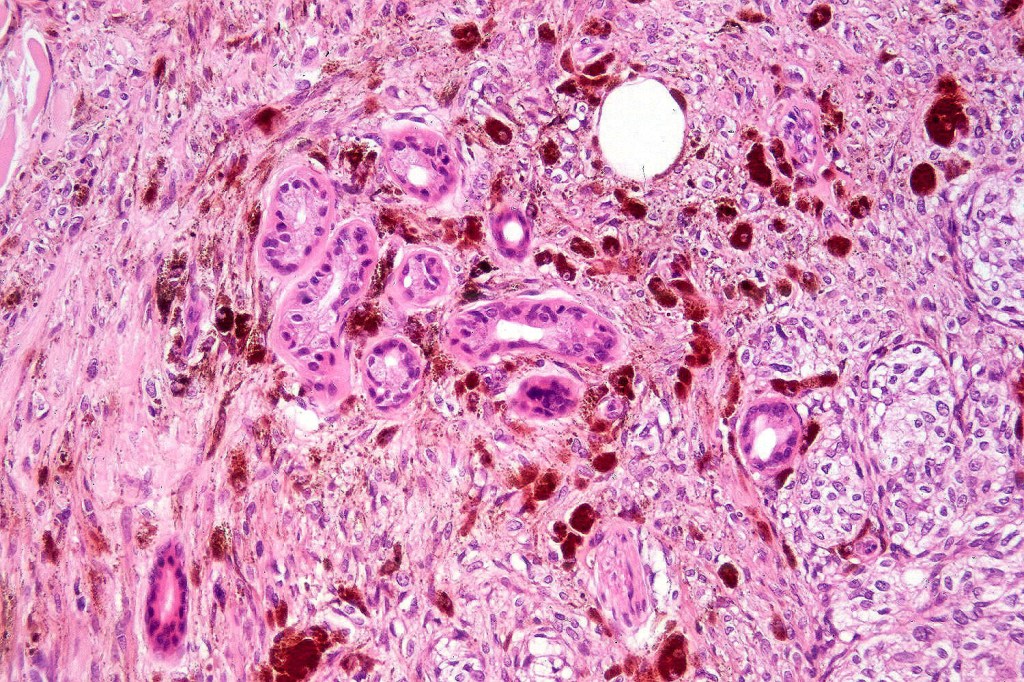

Common blue nevus

Common blue nevus shows a predilection for the backs of the hands & feet, buttocks, face & scalp althought any site can be affected. It presents as a sharply delineated approximately 1.0 cm diameter slate blue or blue/black papulo/nodule. Congenital, eruptive, targetoid, plaque & desmoplatic/hypopigmented variants are recognised. Common blue nevi have also been described in the cervix, oral mucosa, conjunctiva & sclera, breast etc.

Exceptionally, melanoma is a complication

Histologically, it is characterized by a dense population of spindled, dendritic melnanocytes & melanophages with variable fibrosis. It may sometimes represent a component of a combined nevus. Mitotic activity is not usually present and pleomorphism is absent (see atypical blue nevus below). Involvement of the arrector pili muscle is not uncommon.

Very exceptionally, blue nevus also involves the epidermis (compound blue nevus).